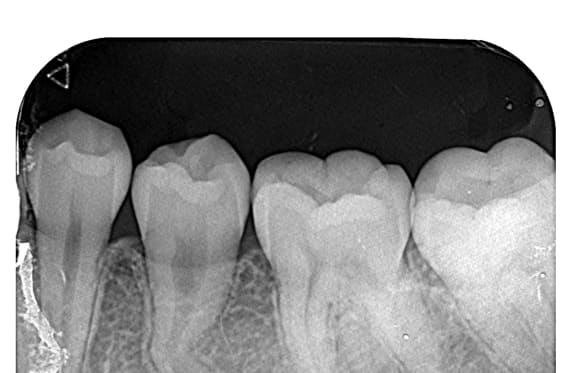

● C4を超え歯根までの虫歯を抜歯、スペースを利用して歯並び全体を整えた症例

藤沢デンタルオフィスの虫歯や破折で抜歯後の部分矯正